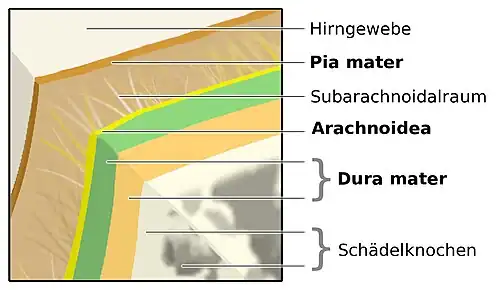

Die Meningitis betrifft alle drei Schichten der Hirnhaut, die zusammen mit Gehirn- und Rückenmarksflüssigkeit (Liquor cerebrospinalis) Gehirn und Rückenmark umschließen und schützen. Die innerste Schicht der Hirnhaut, die Pia mater, ist eine zarte, undurchlässige Schicht, die fest mit der Oberfläche von Gehirn und Rückenmark verbunden ist und auch bis in alle Furchen hinein umschließt. Die mittlere Schicht, die Arachnoidea oder Spinnwebenhaut, sitzt der Pia mater locker auf und „überspringt“ dabei die Furchen des Gehirns. Der Spalt zwischen den beiden Schichten wird als Subarachnoidalraum bezeichnet. Er ist mit Liquor cerebrospinalis gefüllt und heißt, weil er außerhalb des zentralen Nervensystems liegt, auch äußerer Liquorraum. Die äußerste Schicht der Hirnhaut liegt sowohl der Arachnoidea als auch dem Schädelknochen eng an. Sie wird als Dura mater bezeichnet.